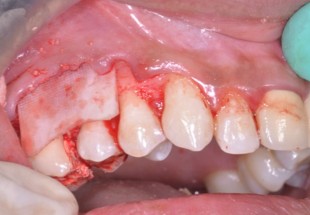

A 22-year old female patient presented in our private dental practice set up with complaint of pain, food stagnation, foul smell and loosening of couple of teeth in upper jaw. Intraoral examination revealed vertical bone loss around distal surface of upper right second premolar and mesial surface of first molar (Figure 1). The pocket depth was measured to be more than 15mm (Figure 2). The severely affected premolar and molar, on pulp testing showed pulpal involvement leading to diagnosis of endo-periodontal lesion.

After 4 weeks, surgical intervention was carried out. Under local anesthesia a full thickness mucoperiosteal flap was reflected to entirely expose the underlying bony defect (Figure 3). Scaling and root planing was again carried out with osteoplasty to make sure the site becomes clean and non-infected. Freeze-dried bone allograft (surreoss) 0.5cc powder was condensed into the bone defect (Figure 4) and 1x2cm Acellular Dermal Matrix Membrane (Surederm) was placed over the graft area to prevent the epithelial cell migration (Figure 5). Finally, interrupted silk (4/0) suture were placed to approximate the soft tissue (Figure 6). Post-operative instructions were given and patient was directed to use chlorhexidine gel and rinse three times for a period of 15 days and suitable antibiotics were prescribed for five days. As the prognosis of tooth was highly questionable patient was recalled on follow up after 1 week, 2 weeks and 4 weeks. After 3-months’ patient’s intraoral radiograph showed remarkable improvement in regard to bone repair and patient’s satisfaction (Figure 7). Clinical evaluation on 3-month, 2-year and 5-year recall exhibited marked reduction in pocket depth up to 12mm with radiographic evidence of further hard tissue repair (Figure 8). A 5-year recall showed a stable probing depth of 3 mm with functionally standing in her oral cavity despite the fact that she refused to have a crown on the treated tooth (Figure 9).